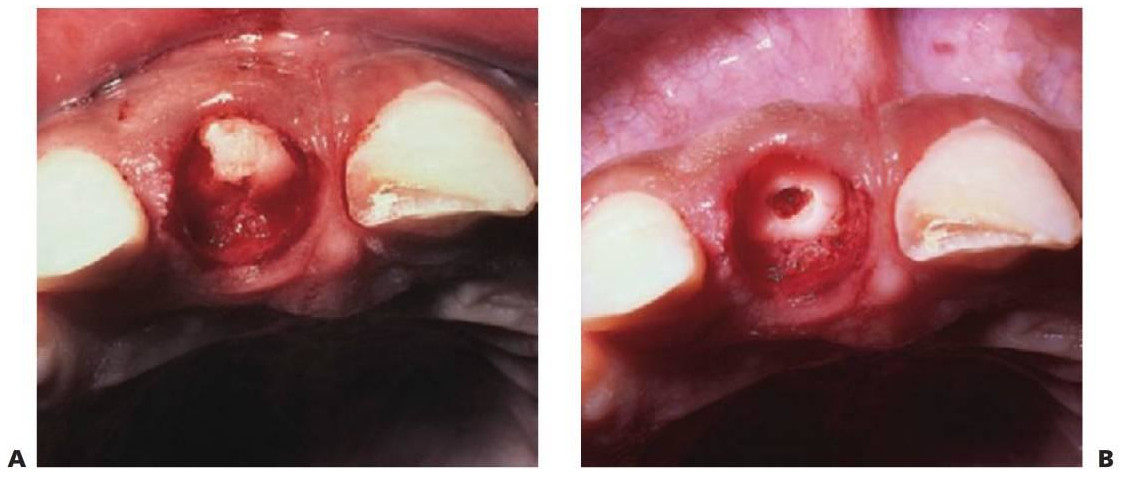

Debido a que el cuello del cóndilo es relativamente más ancho en los niños y tiene un volumen mayor de hueso esponjoso, las fracturas de la superficie articular son más habituales que en los adultos. En los casos de fractura intracapsular (figs. 7.5, 7.9), el seguimiento durante años permite detectar cualquier alteración de su crecimiento, y en los casos en que aparezca una limitación de la apertura o una anquilosis franca, se recomienda una intervención temprana con un injerto costocondral.

Fracturas radiculares

Una fractura que afecte al esmalte, la dentina y el cemento puede o no afectar a la pulpa. La necrosis pulpar se produce en el 25% de los casos, y está relacionada con el grado de desplazamiento de los fragmentos. No es frecuente la reabsorción radicular sustitutiva o inflamatoria progresiva.

Para comprobar la existencia de fracturas radiculares horizontales, se deberá cambiar la angulación vertical de las radiografías periapicales y, cuando se examinan fracturas radiculares verticales, se deberá cambiar la angulación horizontal.

En ocasiones, no se evidencia en un principio una fractura radicular horizontal, ya que el lugar de la fractura se abre bajo la influencia de un exudado inflamatorio varios días después de la lesión. Por tanto, en todo diente traumatizado se debe repetir la radiografía a las 2 semanas (fig. 7.24).